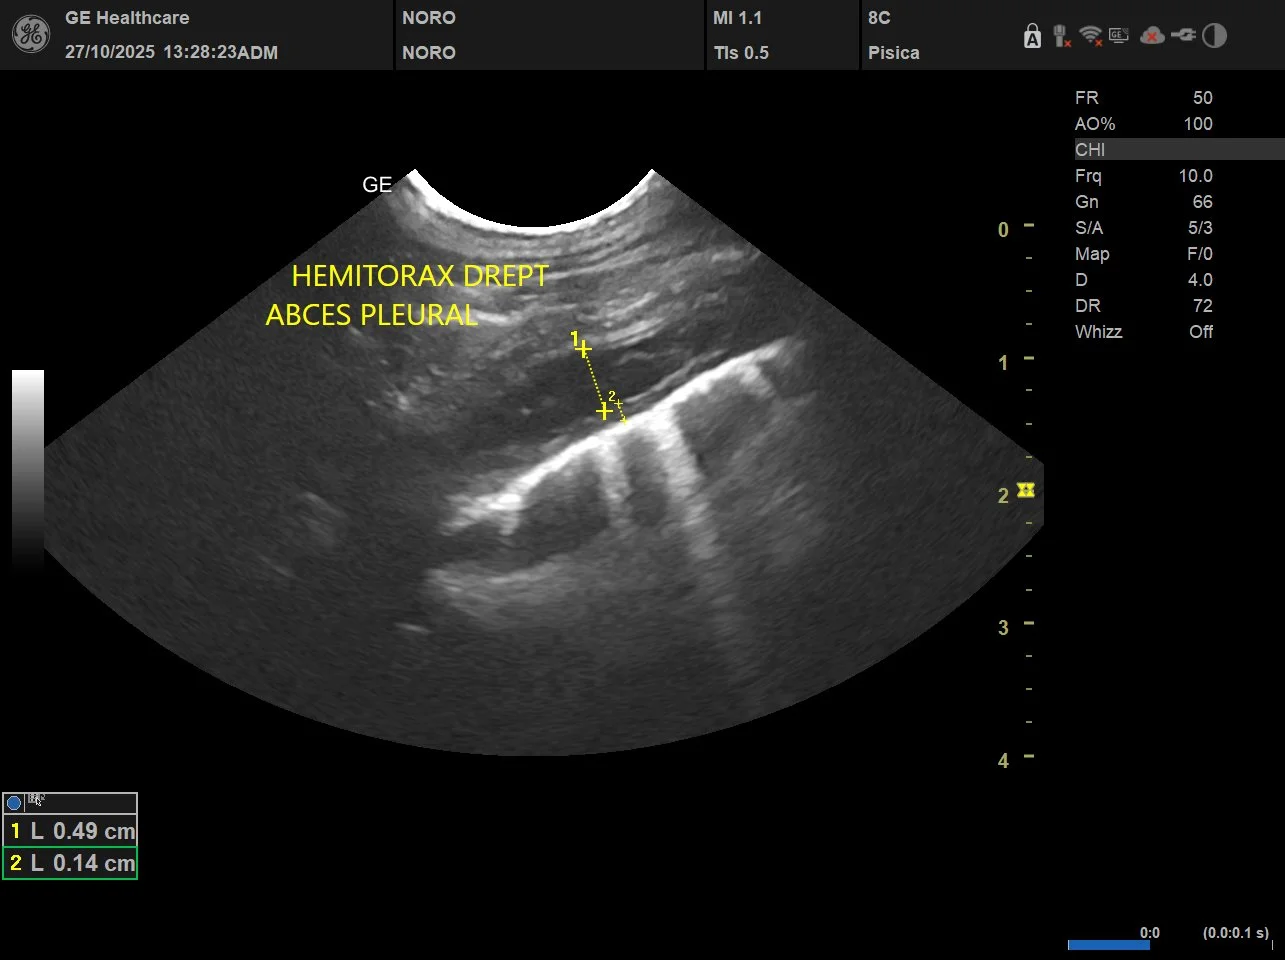

Ecografia este una dintre cele mai valoroase metode de diagnostic imagistic din medicina veterinară modernă. Deși este frecvent asociată cu investigarea unor simptome deja existente, rolul său în prevenție este la fel de important. Prin utilizarea ecografiei în controalele de rutină, multe afecțiuni pot fi depistate din timp, înainte de a provoca durere sau complicații grave.